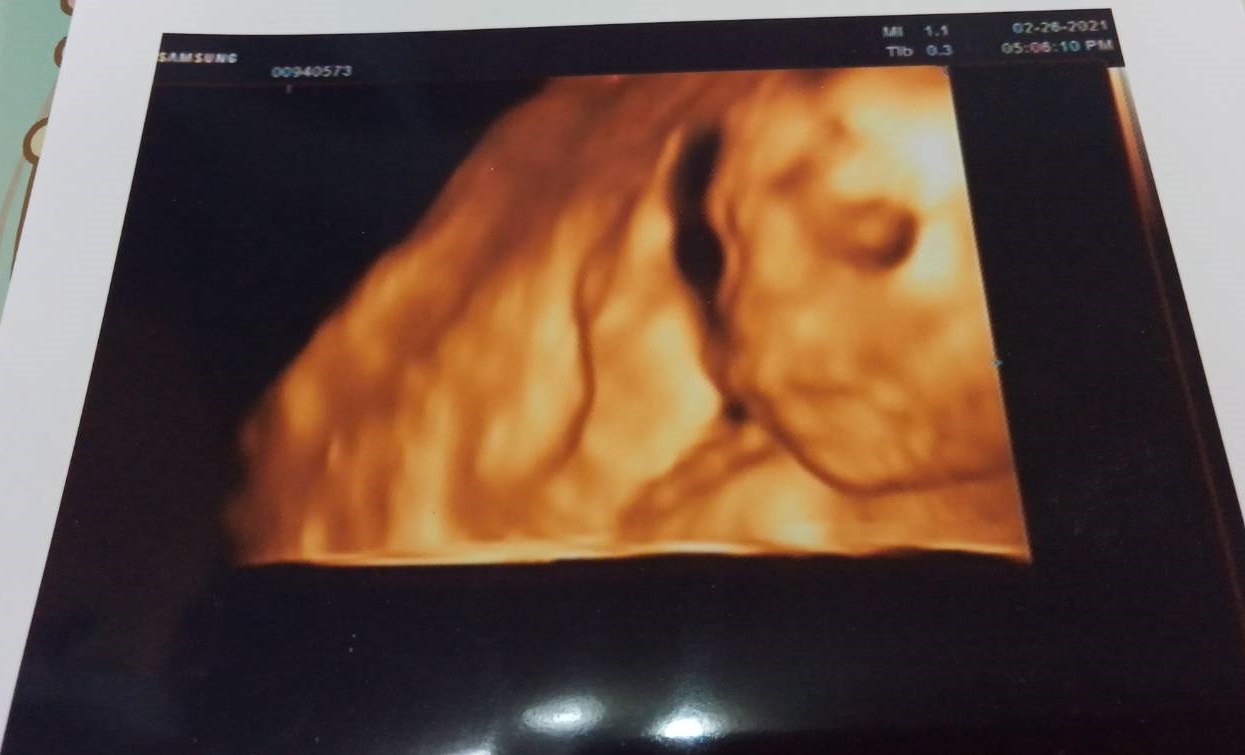

我很幸運,沒有遇到蠻多準媽咪害怕的孕吐,頂多乾嘔而已 有次產檢醫生說我的胎位比較低,要多躺著 所…